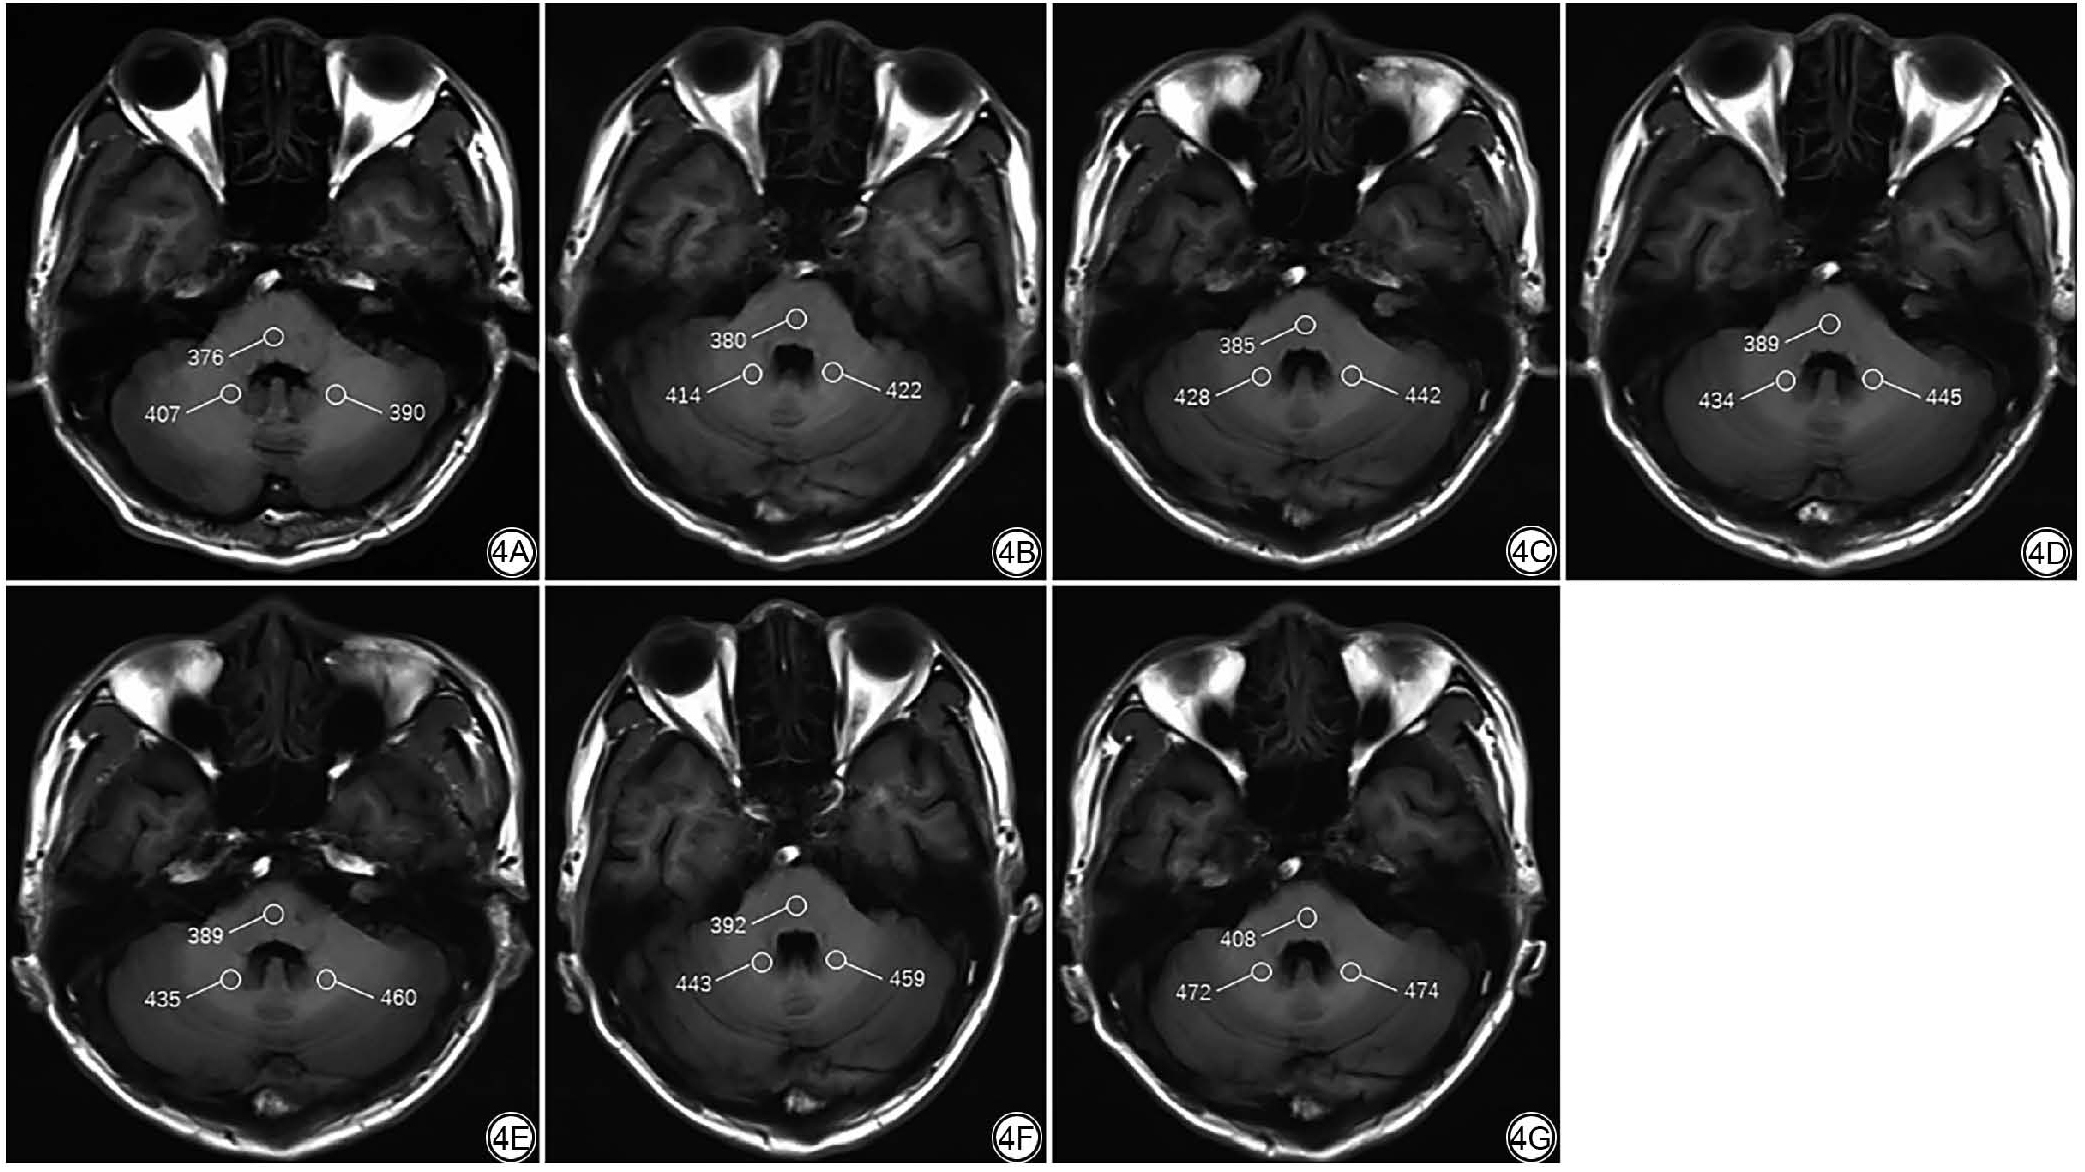

对前6次连续增强的DN/脑桥SI比值的增量进行分析,增量的中位数分别为:1.91、0.94、0.93、0.88、0.91、0.87(图3图4),增量呈减慢的趋势。对增量变化进行趋势性检验,差异具有统计学意义(线性混合效应模型分析结果的系数为-0.215,P<0.001;多项式趋势分析结果的系数为-7.530,P<0.001)。

图3  连续6次增强的患者平扫T1WI齿状核/脑桥SI比值增量的变化。箱式图表示连续MRI检查的数据分布,前四次的增量呈减慢趋势。Rchange定义为同一患者连续前后两次检查的齿状核/脑桥的相对变化的百分比。

图4  男,59 岁,脑胶质瘤。连续6 次增强的患者,感兴趣区及T1WISI 值如图所示。4A:首次MRI 增强前的平扫T1WI;4B~4G:第1-6 次MRI 增强后的平扫T1WI。

Fig. 4  A 59-year-old male with glioma who underwent six consecutive contrast-enhanced MRI scans. The regions of interest and their SI values were as shown in the figure. 4A: The initial non-contrast T1-weighted image obtained prior to the first MRI contrast administration. 4B to 4G: Non-contrast T1-weighted images acquired after the 1st to 6th contrast-enhanced MRI scans, respectively.